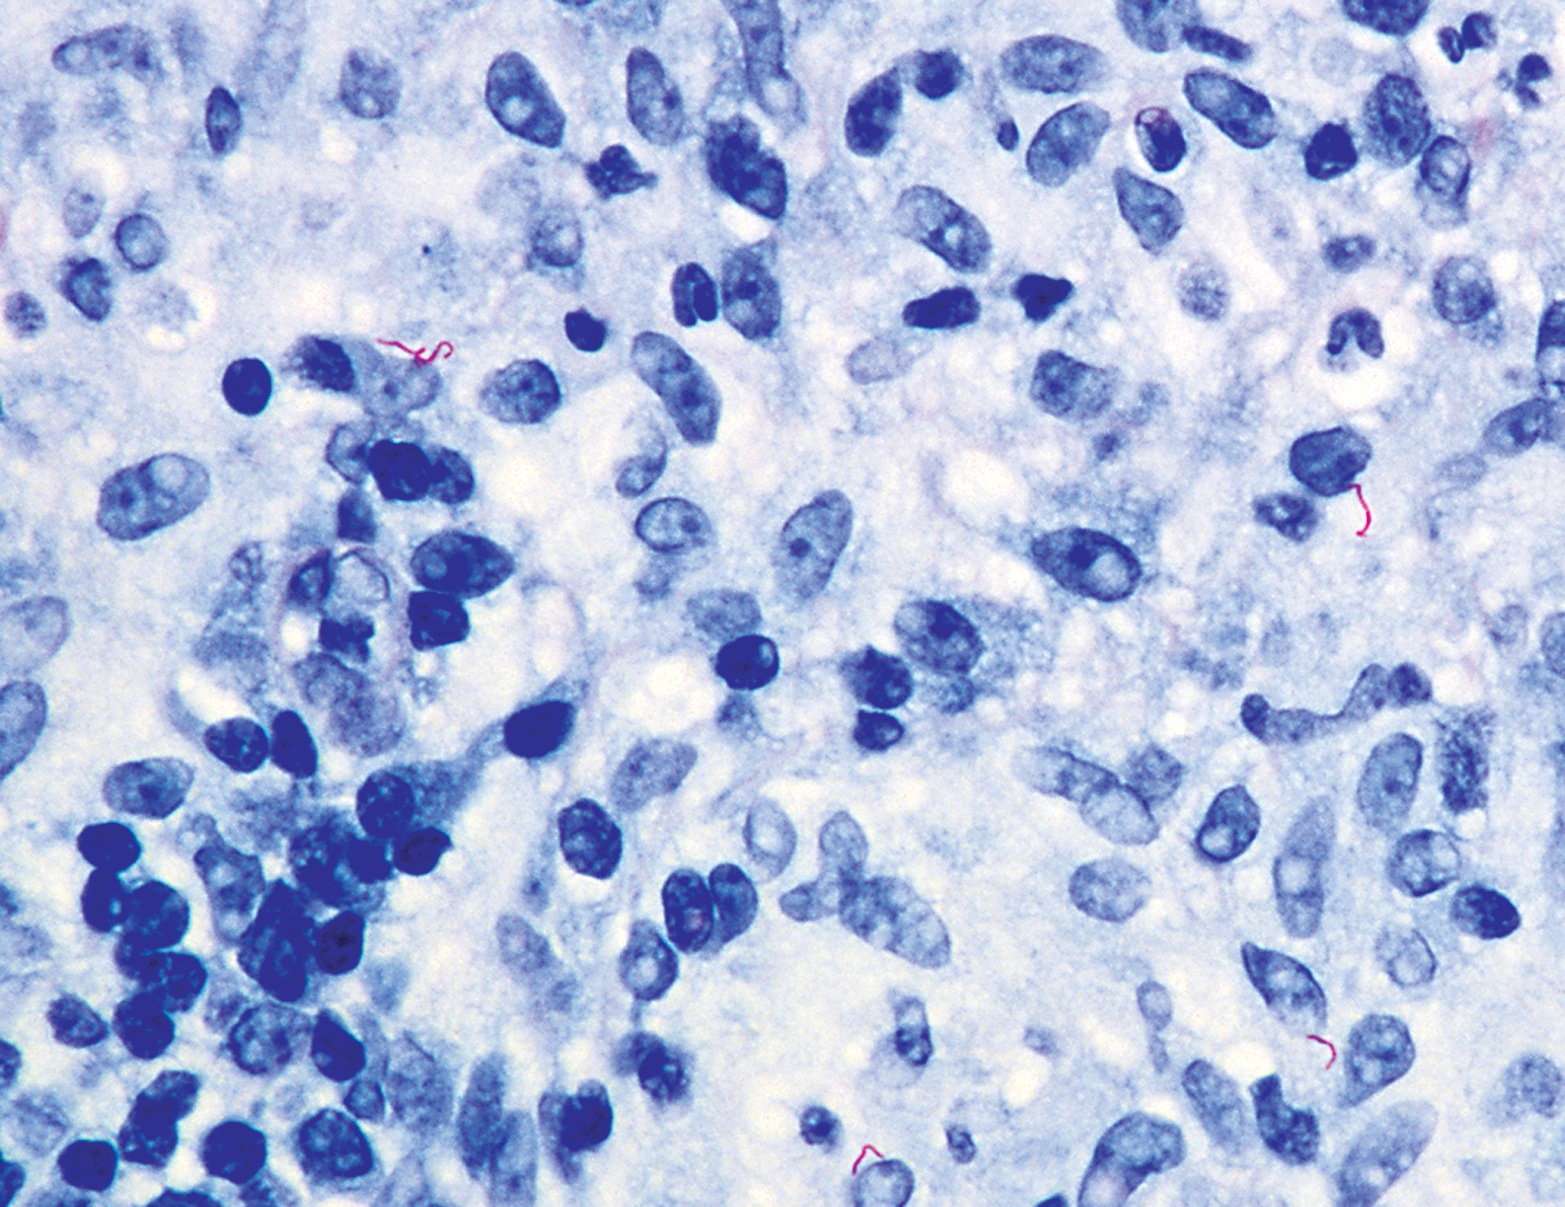

Essential features

- Wuchereria bancrofti accounts for up to 90% of cases

- Diagnosis is typically made by identifying microfilariae in peripheral blood smears

- Rarely, microfilariae are coincidentally detected in FNAC in association with various inflammatory and neoplastic lesions

- Wuchereria bancrofti can be identified by its sheath and multiple, coarse, discrete nuclei extending from head to tail except in the small terminal portion of the caudal end

- Diagnosis is typically made by identifying microfilariae in peripheral blood smears

- Rarely, microfilariae are coincidentally detected in FNAC in association with various inflammatory and neoplastic lesions (J Cytol 2010;27:78, J Cytol 2017;34:43)

- Finding microfilaria in cytosmears is rare

Microscopic (histologic) description

- Wuchereria bancrofti can be identified by its sheath and multiple, coarse, discrete nuclei extending from head to tail except in the small terminal portion of the caudal end

Microscopic (histologic) images

Contributed by Sajna V.M. Kutty, M.D.